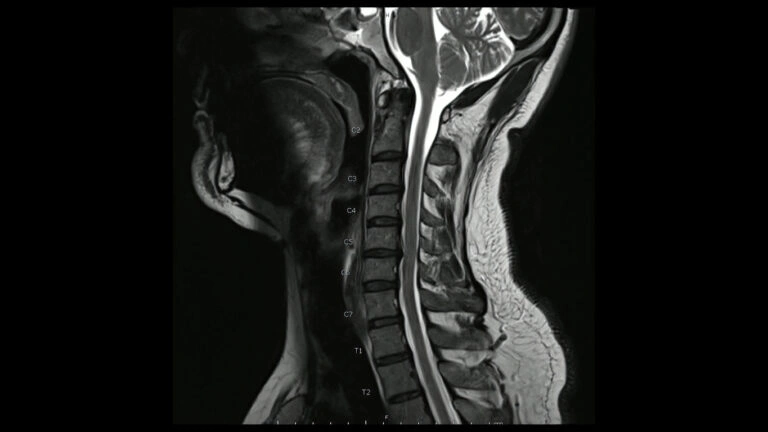

Cervical Degenerative Disc Disease, C5-C6 and C6-C7: Achorage Chiropractor Says: Know the Symptoms!

Degenerative Disc Disease (DDD) in the neck is also called Cervical Disc Disease (CDD). As we age, degeneration of the spine is a common occurrence. The discs that cushion our vertebrae are made largely of water. Over time, they tend to dry up and desiccate. This can lead to pain,